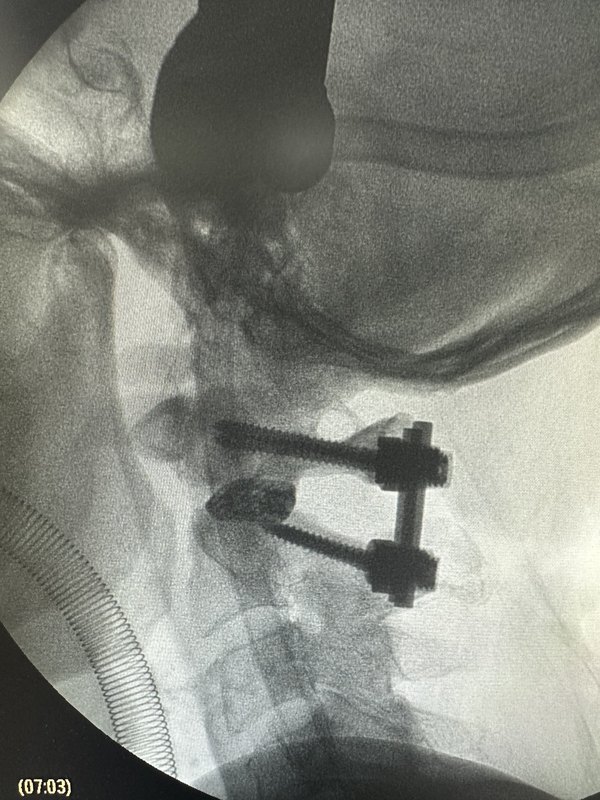

中國(guó)醫(yī)生發(fā)明微創(chuàng)技術(shù)解決寰樞椎脫位寰樞椎脫位可引起延髓、高位頸脊髓受壓,嚴(yán)重者致四肢癱瘓、甚至呼吸衰竭而死亡,需要進(jìn)行手術(shù)治療。經(jīng)典治療方式為頸后路寰樞固定融合術(shù),是由中線切開(kāi)、剝離枕下肌群顯露寰、樞椎椎板進(jìn)行手術(shù)。該入路切開(kāi)或切斷的韌帶及肌肉包括:淺層的項(xiàng)韌帶、斜方肌、頭夾??;深層的頭半棘肌、頸半棘肌、頭后大直肌、頭后小直肌、頭下斜肌。研究顯示,上述韌帶和肌肉的破壞,尤其是樞椎棘突附著肌肉附著點(diǎn)的破壞,是開(kāi)放寰樞椎固定術(shù)后軸性疼痛的原因。文獻(xiàn)報(bào)告,其開(kāi)放術(shù)后的頸部肌肉疼痛、痙攣及功能障礙的發(fā)生率可達(dá)18–60%。術(shù)后枕頸部疼痛是開(kāi)放式寰樞椎融合術(shù)后常見(jiàn)并發(fā)癥,為影響術(shù)后快速康復(fù)的因素之一。為此,北醫(yī)三院骨科王圣林主任團(tuán)隊(duì)世界首創(chuàng)設(shè)計(jì)出—微創(chuàng)肌間隙寰樞側(cè)塊融合技術(shù)(Minimalinvasivesurgery-posterioratlantoaxiallateralmassjointfusion,Mis-PALF)。Mis-PALF可保護(hù)枕頸區(qū)后方肌肉的附著點(diǎn),可大大減輕術(shù)后枕頸部疼痛及麻木癥狀、減少圍手術(shù)期失血。這一由我國(guó)醫(yī)師原創(chuàng)設(shè)計(jì)的入路在多次國(guó)際會(huì)議上獲得廣泛關(guān)注。并于2024年9月發(fā)表在國(guó)際骨科頂級(jí)雜志JBJS雜志,獲得國(guó)際同行認(rèn)可。寰樞椎微創(chuàng)手術(shù)Mis-PALF是經(jīng)過(guò)頸部肌肉間隙,保留枕頸部肌肉止點(diǎn),將肌肉損傷降至最低。術(shù)后患者的頸部疼痛不適下降60%。術(shù)后無(wú)引流管,24小時(shí)下地拍片,術(shù)后第二天即可出院回家、術(shù)后1個(gè)月恢復(fù)工作。目前,Mis-PALF技術(shù)已經(jīng)在北醫(yī)三院實(shí)施6年、超過(guò)300例患者接受此手術(shù)、并發(fā)癥低于1%;國(guó)內(nèi)多家醫(yī)院推廣使用,其安全性、有效性獲得廣泛好評(píng)。請(qǐng)廣大寰樞椎疾病患者關(guān)注此技術(shù),將大大降低寰樞椎手術(shù)的創(chuàng)傷和風(fēng)險(xiǎn)。?文章引用鏈接:HungKL,LuY,TianY,XueS,GaoG,GaoQ,XuN,WangS.MinimallyInvasiveSurgeryforPosteriorAtlantoaxialLateralMassJointFusion(MIS-PALF):AMuscle-SparingProcedureforAtlantoaxialInstabilityorDislocation.JBoneJointSurgAm.2024Sep18.doi:10.2106/JBJS.23.01464.Epubaheadofprint.PMID:39292794.

寰樞椎脫位是一種嚴(yán)重疾病,由于寰椎向前或向后脫位,引起上部頸髓受壓,導(dǎo)致患者出現(xiàn)四肢癱瘓,甚至呼吸肌麻痹而死亡,必須及時(shí)進(jìn)行救治。寰樞椎脫位的病因可分為外傷性、先天性和病理性三大類。在我國(guó),以外傷性寰樞椎脫位多見(jiàn),先天畸形性寰樞椎脫位其次,而病理性寰樞椎脫位相對(duì)少見(jiàn)。外傷性寰樞椎脫位占頸部骨折脫位的10%~14%。常見(jiàn)原因有齒突骨折和橫韌帶損傷,橫韌帶損傷可分為韌帶本身的斷裂以及骨附著部撕脫。此外翼狀韌帶損傷可引起寰樞旋轉(zhuǎn)不穩(wěn)。關(guān)節(jié)囊、覆膜、寰樞副韌帶等其他韌帶損傷以及某些寰椎和樞椎體骨折也會(huì)導(dǎo)致寰樞椎不穩(wěn)與脫位。先天性寰樞椎脫位的常見(jiàn)原因?yàn)辇X突發(fā)育異常、先天性寰枕融合、Klippel-Feil綜合征、顱底凹陷等先天畸形。其中齒突畸形最為常見(jiàn),包括齒突缺如、齒突發(fā)育不全和游離齒突等三種類型。齒突生理功能不全或喪失,使齒突在寰椎前弓和橫韌帶之間的穩(wěn)定的扣鎖關(guān)系減弱或消失,使寰椎在樞椎上活動(dòng)范圍異常增大。而在寰枕融合或Klippel-Feil綜合征或顱底凹陷患者,寰樞關(guān)節(jié)負(fù)荷增加,代償性活動(dòng)加大,累積性勞損將使寰樞間韌帶和關(guān)節(jié)囊松弛,逐漸發(fā)生寰樞椎不穩(wěn)和脫位。引起寰樞椎脫位與不穩(wěn)的病理性因素較常見(jiàn)的有感染性炎癥和類風(fēng)濕關(guān)節(jié)炎。蔓延至寰樞椎的感染性炎癥所致脫位與不穩(wěn)絕大多數(shù)發(fā)生于兒童,通常稱為自發(fā)性寰樞椎脫位,其機(jī)制為炎性因素導(dǎo)致關(guān)節(jié)囊和周圍韌帶松弛,并發(fā)的肌肉痙攣及持續(xù)的頸項(xiàng)強(qiáng)直也加劇脫位。類風(fēng)濕關(guān)節(jié)炎引起的寰樞椎脫位與不穩(wěn)多為成人,歐美國(guó)家常見(jiàn)而我國(guó)少見(jiàn)。類風(fēng)濕過(guò)程的破壞性炎癥改變和繼發(fā)于脈管炎的組織變性導(dǎo)致韌帶和關(guān)節(jié)囊松弛,這種慢性炎癥過(guò)程還引起鄰近骨破壞和關(guān)節(jié)滑膜肉芽組織形成;寰椎側(cè)塊骨丟失及隨后的樞椎上移導(dǎo)致顱底下沉,陷人的齒突和(或)肉芽組織可構(gòu)成對(duì)延脊髓腹側(cè)的壓迫。另外,結(jié)核和腫瘤等直接破壞骨性和韌帶結(jié)構(gòu),也可引起寰樞椎脫位與不穩(wěn)。按脫位方向可分為前脫位、后脫位和旋轉(zhuǎn)脫位。按能否復(fù)位可分為易復(fù)性、難復(fù)性和不可復(fù)性。經(jīng)頭頸雙向牽引能復(fù)位的為易復(fù)性,頭頸雙向牽引不能完全復(fù)位但減壓松解術(shù)后牽引能復(fù)位的為難復(fù)性,頭頸雙向牽引及減壓松解術(shù)后再牽引仍不能復(fù)位的為不可復(fù)性。陳舊性損傷或畸形多為難復(fù)性和不可復(fù)性脫位,不能復(fù)位的原因有寰樞外側(cè)關(guān)節(jié)交鎖、肉芽瘢痕增生、齒突骨折畸形愈合、寰樞關(guān)節(jié)破壞強(qiáng)直和韌帶的嵌壓等。外傷性寰樞椎脫位有明確的外傷史,但有些患者外傷并不嚴(yán)重而易引起漏診。傷后即刻部分患者即表現(xiàn)出寰樞椎脫位,另一部分則漸進(jìn)出現(xiàn)脫位。臨床表現(xiàn)有:①局部癥狀與體征:頸項(xiàng)肌痙攣和疼痛,頸項(xiàng)活動(dòng)受限;頸部失落感,常需雙手托住下頜,頭部不敢活動(dòng);頭頸部偏斜。②頸髓受壓表現(xiàn):嚴(yán)重的頸髓損傷多因呼吸肌麻痹而死于現(xiàn)場(chǎng),能運(yùn)送至醫(yī)院者多為頸髓不完全性損傷,根據(jù)脊髓損傷的輕重可出現(xiàn)不同程度的四肢感覺(jué)、運(yùn)動(dòng)和反射障礙。③部分患者在外傷后逐漸出現(xiàn)寰樞椎脫位,由于椎動(dòng)脈穿行于橫突孔并從寰椎上方穿出,過(guò)度活動(dòng)可刺激椎動(dòng)脈導(dǎo)致痙攣或閉塞,出現(xiàn)頭暈、一過(guò)性昏迷等椎-基底動(dòng)脈供血不足癥狀。先天畸形性寰樞椎脫位多為無(wú)明顯誘因緩慢發(fā)病,癥狀呈間歇性,反復(fù)多次發(fā)作并緩慢加重。首發(fā)癥狀多為四肢無(wú)力、步態(tài)不穩(wěn)、四肢麻木,四肢麻木可單肢或雙上肢或雙下肢。其次是頭痛、頭暈,頭痛以枕部為多。少數(shù)患者有飲水嗆咳、吞咽困難、聲音嘶啞等。一般體征:短頸畸形、后發(fā)際低、頭頸部活動(dòng)受限、斜頸及翼狀肩等。神經(jīng)癥狀和體征:由于頸椎畸形,椎管狹窄和小腦扁桃體下降自背側(cè)壓迫上頸髓,多出現(xiàn)肢體感覺(jué)運(yùn)動(dòng)障礙和椎體束征,多見(jiàn)下肢肌張力增高、腱反射亢進(jìn)和病理反射等。自發(fā)性寰樞椎脫位大多發(fā)生于小兒,多繼發(fā)于咽喉或枕頸區(qū)感染,常表現(xiàn)為持續(xù)性頸部疼痛及活動(dòng)受限,并呈逐漸緩慢加重,且常為單側(cè)旋轉(zhuǎn)性脫位,早期易復(fù)位,后期可發(fā)展為固定性旋轉(zhuǎn)畸形。類風(fēng)濕寰樞椎脫位具有類風(fēng)濕關(guān)節(jié)炎的病史和癥狀。X線片包括頸椎正側(cè)位、張口位片,必要時(shí)可行動(dòng)態(tài)側(cè)位照片、顱骨照片和一些特殊位置照片。CT可以更清晰的顯示骨性結(jié)構(gòu)及其關(guān)系。MRI可直接顯示脊髓、腦干及小腦等神經(jīng)結(jié)構(gòu)受壓和變性情況,應(yīng)用動(dòng)態(tài)MRI可觀察局部失穩(wěn)對(duì)神經(jīng)的動(dòng)態(tài)刺激或壓迫;MRI也可直接顯示寰椎橫韌帶受損情況。寰齒前間隙:為寰椎前結(jié)節(jié)后緣與齒突前緣間隙。正常成人<3mm,過(guò)屈過(guò)伸時(shí)無(wú)變化;兒童<4mm,過(guò)屈過(guò)伸時(shí)差值<1mm。寰樞椎前脫位或半脫位時(shí)此間隙可增寬,如超過(guò)5mm以上,則考慮有寰椎橫韌帶松弛或斷裂。寰椎兩側(cè)緣與樞椎體兩側(cè)緣正常情況下應(yīng)是連續(xù)的,若發(fā)生同向不連續(xù)則表示寰椎側(cè)方移位;若兩側(cè)離心分離之和>6.9mm,則可能有寰椎橫韌帶斷裂。寰樞椎脫位的診斷通過(guò)影像學(xué)檢查并不困難,關(guān)鍵是骨科醫(yī)師要考慮到此病。外傷性寰樞椎脫位雖然多有明確的外傷史,但在臨床上造成漏診和誤診者并不少見(jiàn),原因?yàn)椋孩俸喜⒌娘B腦外傷干擾了對(duì)頸椎損傷的診斷;②外傷后逐漸出現(xiàn)的寰樞椎脫位,逐漸發(fā)生的脊髓壓迫癥狀;③陳舊性脫位,癥狀體征不典型,外傷史不明確。由于枕頸部先天性畸形臨床表現(xiàn)的多變性,而且癥狀通常隱匿、體征定位困難,故臨床有如下表現(xiàn)應(yīng)懷疑有顱頸交界區(qū)先天性畸形的存在:①青壯年發(fā)病,癥狀間歇呈漸進(jìn)性加重,無(wú)明顯誘因或輕微創(chuàng)傷誘發(fā)發(fā)病。②頭頸部畸形,發(fā)際低平、短頸、頭頸活動(dòng)受限。③枕項(xiàng)疼痛、疲勞感或麻木無(wú)力。④復(fù)雜的難以解釋的神經(jīng)學(xué)癥狀。寰樞椎脫位外科治療的目的為:解除脊髓壓迫,穩(wěn)定脊柱節(jié)段,防止繼發(fā)損傷。非手術(shù)治療的方法有牽引、外固定和功能鍛煉,手術(shù)治療方法通常有減壓復(fù)位術(shù)和內(nèi)固定融合術(shù)。治療方法的選擇取決于寰樞椎脫位的類型、病因以及并發(fā)神經(jīng)損傷的情況。治療程序一般先行牽引,判斷脫位是可復(fù)性還是不可復(fù)性,對(duì)不可復(fù)性脫位需行手術(shù)治療,可復(fù)性脫位根據(jù)病因不同可行手術(shù)治療或非手術(shù)治療;如果非手術(shù)治療效果欠佳,則應(yīng)二期手術(shù)治療。如果存在不可復(fù)位的延脊髓壓迫或伴有腦脊液循環(huán)障礙,應(yīng)盡快行減壓術(shù)。原則上腹側(cè)壓迫經(jīng)口前路減壓,背側(cè)壓迫行后路減壓,減壓的范圍視具體情況可擴(kuò)大到枕骨大孔區(qū)甚至顱后窩。對(duì)于橫韌帶斷裂,如果能確診,應(yīng)一期行寰樞融合術(shù)??梢蓹M韌帶斷裂時(shí),可先行外固定治療。而對(duì)于橫韌帶附著點(diǎn)的撕脫性損傷,因預(yù)后較好,應(yīng)先行外固定。外固定治療3~4月后如存在持續(xù)性不穩(wěn),應(yīng)行寰樞融合術(shù)。先天性寰樞椎脫位,因畸形持續(xù)存在,脫位多為難復(fù)性或不可復(fù)性且呈漸進(jìn)性加重,非手術(shù)治療效果差。因?yàn)轱B頸交界區(qū)畸形多為多種畸形合并存在,先天性寰樞椎脫位與不穩(wěn)常需行枕頸融合術(shù)。自發(fā)性寰樞椎脫位牽引效果好,復(fù)位后予以適當(dāng)外固定并加強(qiáng)功能鍛煉,常能獲得較滿意的療效。類風(fēng)濕關(guān)節(jié)炎引起的寰樞椎脫位,病程為慢性進(jìn)行性,病變累及范圍較廣,可先行非手術(shù)治療,如效果欠佳(存在神經(jīng)壓迫時(shí)),則應(yīng)行減壓融合術(shù)。對(duì)于結(jié)核或腫瘤引起的寰樞椎脫位與不穩(wěn),除治療脫位與不穩(wěn)外,還應(yīng)處理原發(fā)病灶。

一、什么是寰樞椎脫位l?人體的頸椎一共七塊,寰椎和樞椎分別是指第一塊和第二塊頸椎。寰樞椎脫位是指由于創(chuàng)傷、先天畸形、炎癥或手術(shù)等因素造成寰樞椎關(guān)節(jié)面失去正常對(duì)合關(guān)系,發(fā)生關(guān)節(jié)功能障礙和(或)神經(jīng)壓迫的病理狀態(tài)。l?可能發(fā)生于各個(gè)年齡段,主要癥狀表現(xiàn)為頸項(xiàng)部疼痛,四肢麻木無(wú)力。二、寰樞椎脫位術(shù)后注意事項(xiàng)寰樞椎脫位術(shù)后注意事項(xiàng)1、下地活動(dòng):一般術(shù)后12小時(shí)后可以離床活動(dòng)。2、體位:手術(shù)后在拆線以前,應(yīng)采用側(cè)臥位為主,避免長(zhǎng)時(shí)間仰臥壓迫傷口,影響傷口愈合。睡眠時(shí)選擇一合適頸椎生理曲度的枕頭,側(cè)臥時(shí),枕頭的高度可以大約等于一側(cè)肩寬的高度。3、飲食:可以正常飲食,多吃高鈣、高維生素、高蛋白食物,促進(jìn)傷口愈合。4、頸托保護(hù):術(shù)后2月內(nèi)平時(shí)和出門、乘車時(shí)均需要佩戴頸托,2月之后平時(shí)不需要佩戴,頸部可以適度自由活動(dòng),但出門和乘車時(shí)還需要佩戴,以防摔倒或者急剎車導(dǎo)致頸部外傷,至術(shù)后3個(gè)月可不佩戴頸托。5、拆線:手術(shù)術(shù)后2周拆線,拆線1周后血痂自然脫落后可淋浴,術(shù)后1月可用浴液清洗。6、術(shù)后復(fù)查:術(shù)后定期復(fù)查,建議術(shù)后3個(gè)月、術(shù)后半年、術(shù)后1年、術(shù)后2年各復(fù)查一次。出院后任何時(shí)候出現(xiàn)癥狀反復(fù)、肢體無(wú)力等應(yīng)及時(shí)復(fù)查。7、功能鍛煉:術(shù)后2月后應(yīng)可適度開(kāi)始頸部拉伸活動(dòng),增加瘢痕的彈性。術(shù)后3個(gè)月一般植骨間隙開(kāi)始融合,可以做有阻力的頸部屈伸、旋轉(zhuǎn)活動(dòng),功能鍛煉要循序漸進(jìn),若出現(xiàn)頸部不適時(shí)應(yīng)暫時(shí)停止。8、出院后藥物:必要時(shí)遵醫(yī)囑繼續(xù)口服一些神經(jīng)營(yíng)養(yǎng)藥物,如甲鈷胺等。如合并風(fēng)濕等疾病,應(yīng)到相應(yīng)科室就診治療。期間如果有任何疑問(wèn)或不適,請(qǐng)及時(shí)咨詢主治醫(yī)師。